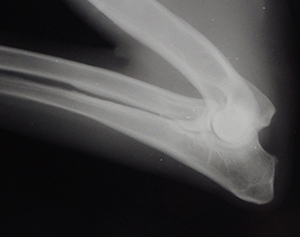

@ 34.5 months OFA Elbows Normal Rt. Elbow

Lt Elbow

OFA Excellent Hips @ 34.5 mos